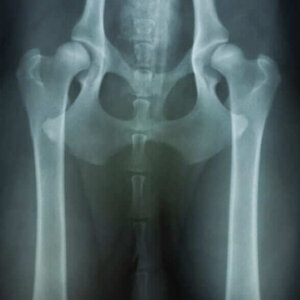

Navicular syndrome is a very common problem in the equine industry, likely impacting 30% or more of horses, dependent on the breed and discipline. We see this condition commonly in the western disciplines but also to varying degrees in other sports, including jumping, dressage and even racing. There are many factors that contribute to the problem, which can make it difficult at times to manage. All too often, though, we tend to wait until the condition has progressed, with irreversible damage, before we properly intervene. With a better understanding, hopefully we can recognize the condition sooner, see contributing factors and produce better results for the patient in the long term.